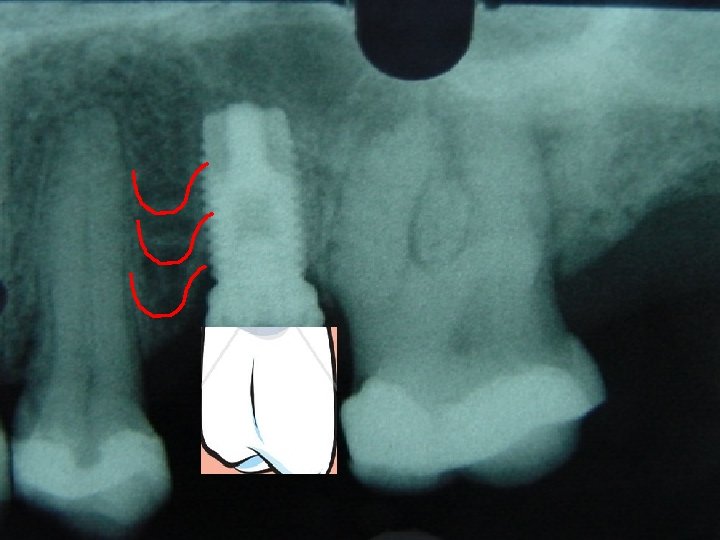

IMPLANTE: DOR: “ Onde há dor há fracasso” Fixação Rígida: mobilidade Horizontal pós carga Mobilidade horizontal pré-carga Mobilidade vertical Profundidade com Sonda: subjetivo; mais de 6 mm favorece infecção. Perda Óssea: rx inicial, quantificar perda óssea – crista alveolar referencial. Índice de Sangramento: subjetivo

IMPLANTE: Índice de Sangramento: subjetivo Doença Periimplantite: GUNA, placa dental, medicamentosa, hormonal PERIOIMPLANTITE. Percussão: Subjetivo ; só para avaliar dor Avaliação Radiográfica: crista óssea

IMPLANTE: “ Quando houver mobilidade horizontal maior do que 1 mm, qualquer mobilidade vertical, rápida perda óssea progressiva, dor a percussão, dor a função”. MISCH (1996 )